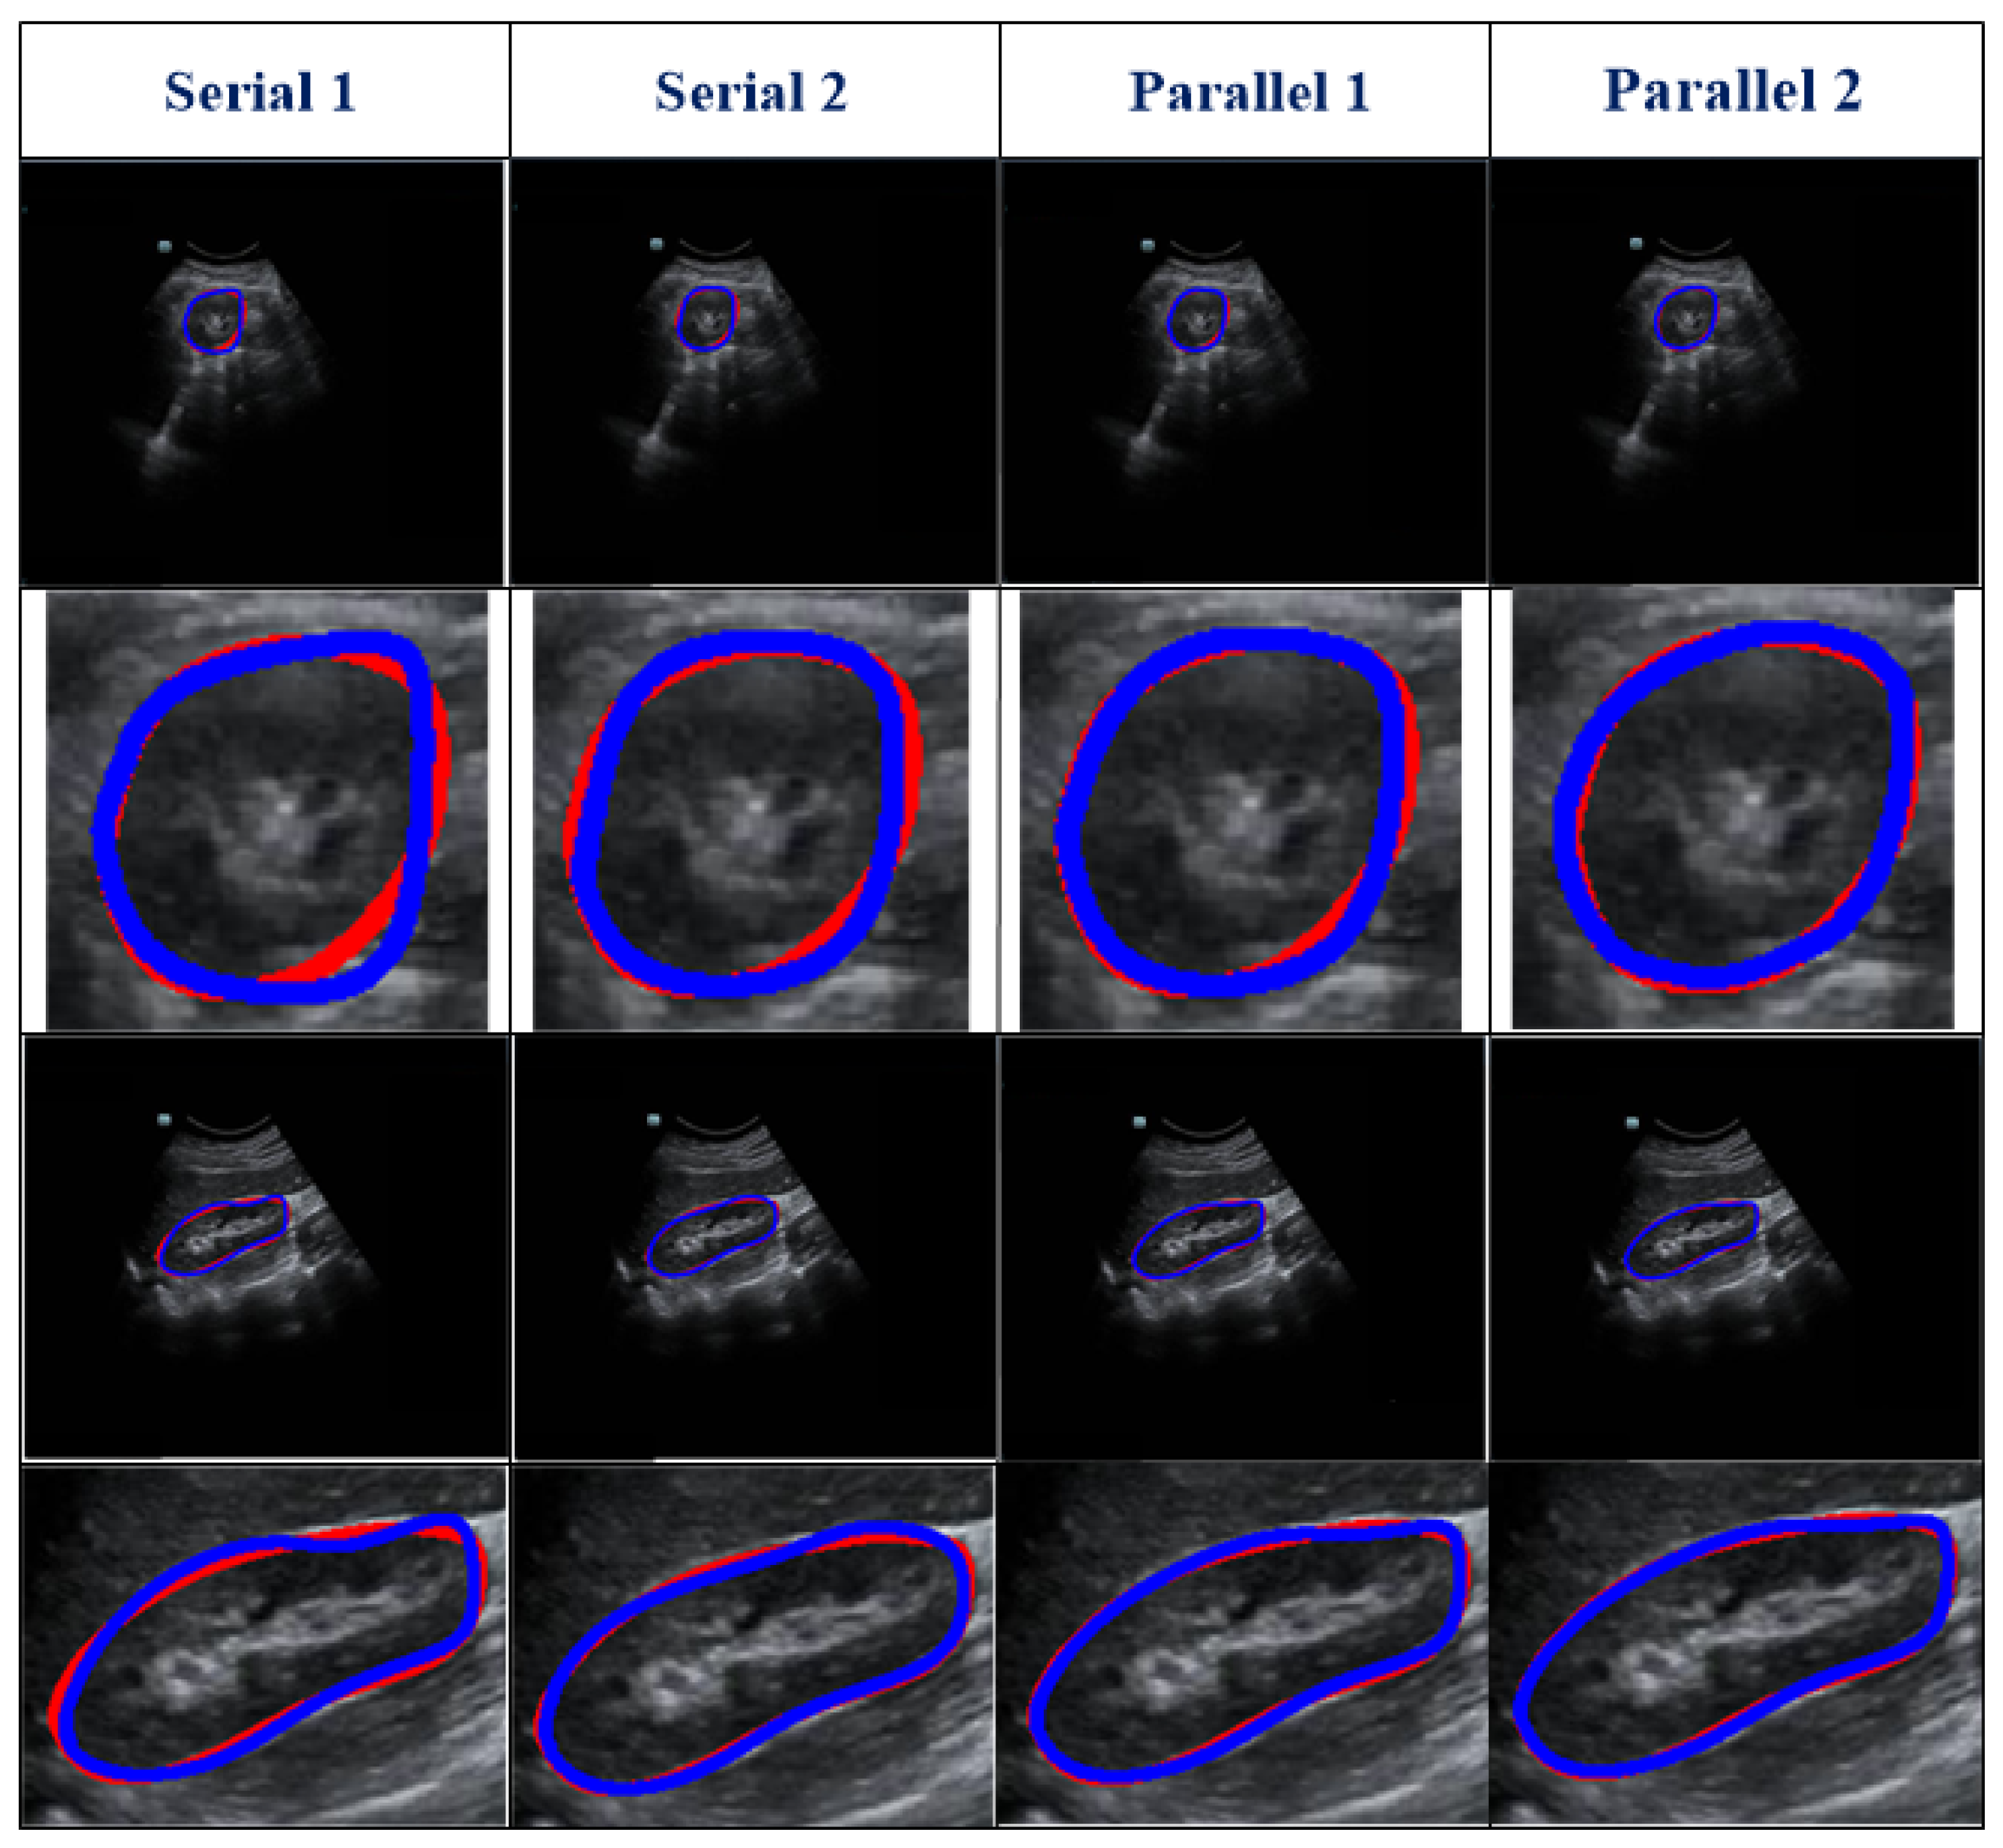

Our work used a DFLN for coarse kidney segmentation, where the DFLN model comprises an SE module [19], an AG module [33], and a U-Net architecture [20]. As the SE and AG modules have a good ability to highlight salient features, we used both to generate different fusion variants. Figure 3 shows the structure of four fusion variants (two serial and two parallel). The combination of the AG and SE modules occurs at each skip connection of the U-Net structure.

With the U-Net structure as the backbone, we used one serial architecture of AG followed by SE (Serial 1) and another serial architecture of SE followed by AG (Serial 2). Furthermore, using different inputs for the SE module, we used different parallel architectures. The biggest difference between the two parallel architectures lies in the input for the SE: one uses features from decoding paths (Parallel 1) and the other uses features from encoding paths (Parallel 2).

The U-Net structure contains encoder and decoder blocks. The SE module contains a squeeze module (global max-pooling layer) and an excitation module (two 1 × 1 convolutions followed by a ReLU [26] and sigmoid function [34]). In addition, the AG module contains a concatenation between the output of the corresponding down-sampled and up-sampled layers, each followed by the ReLU, a 1 × 1 convolution, a sigmoid function, and a multiplication operation.

As shown in Table 2, different serial and parallel architectures resulted in different levels of performance for the coarse segmentation strategy. There are three aspects of the outcomes presented in Table 2 to be discussed. First, overall, the parallel architecture showed better capability than the serial architecture. Both the AG [18] and SE [19] modules are known to have a good ability to boost relevant features and remove irrelevant features. However, using serial AG and SE modules may cause the deletion of a large amount of information, some of which may be useful. Second, of the serial architectures evaluated, SE-AG (Figure 3b) showed better performance than AG-SE (Figure 3a). The main reason for this is that the AG module has a more complex structure than the SE module (as shown in Section 2.3), which makes it difficult to train the AG module and avoid the loss of meaningful information. Third, as illustrated in Table 2, the Parallel 2 model performed better than the Parallel 1 model. The main difference between these two parallel architectures is in the input for the SE module, with one using features from the decoding path (Parallel 1) and the other using features from the encoding path (Parallel 2). Parallel 2 may perform better because using encoding features as the input for the SE module carries the merit of the SE module to emphasize meaningful features and suppress less useful features.

Figure 3. Description of the variants’ architecture, where (a) represent serial AG followed by SE, (b) represent the serial SE followed by AG, and (c) show both parallel architectures.